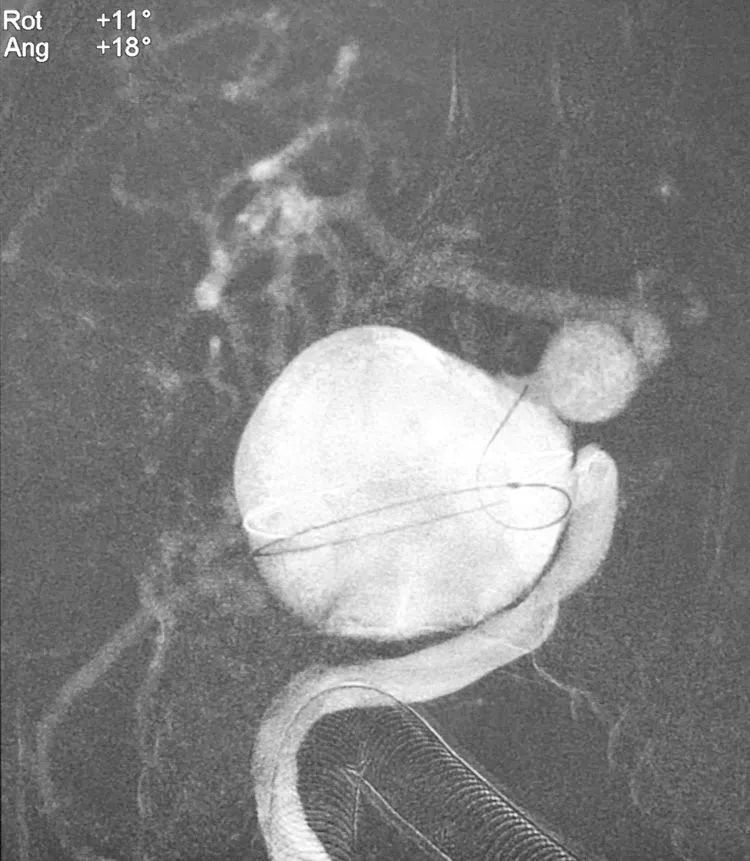

右颈内动脉工作位路图下,5F Navien中间导管抵达右颈内动脉破裂孔段,Synchro-14微导丝携带Echelon-10微导管经5F Navien送入近端大瘤的瘤腔,试图成袢越过大瘤,再越过远端小瘤,继而跋涉至大脑中动脉;随后将使用“拉直成袢”技术和交换技术把T-Track支架导管交换入大脑中动脉。

然而,出师未捷,Synchro-14微导丝只能勉强搭住大瘤出口,转来转去无法继续前行,巨大的瘤腔像无底洞,只能进不能出。

计划不如变化,决定一期先用弹簧圈填塞大瘤,隔至少一个月后再二期置放密网支架。双微管依次、交替填入11枚弹簧圈(MicroPlex 18-24-68-Cosmos Complex 九枚,MicroPlex 18-20-65-Cosmos Complex,QC-20-50-3D),部分栓塞大瘤。